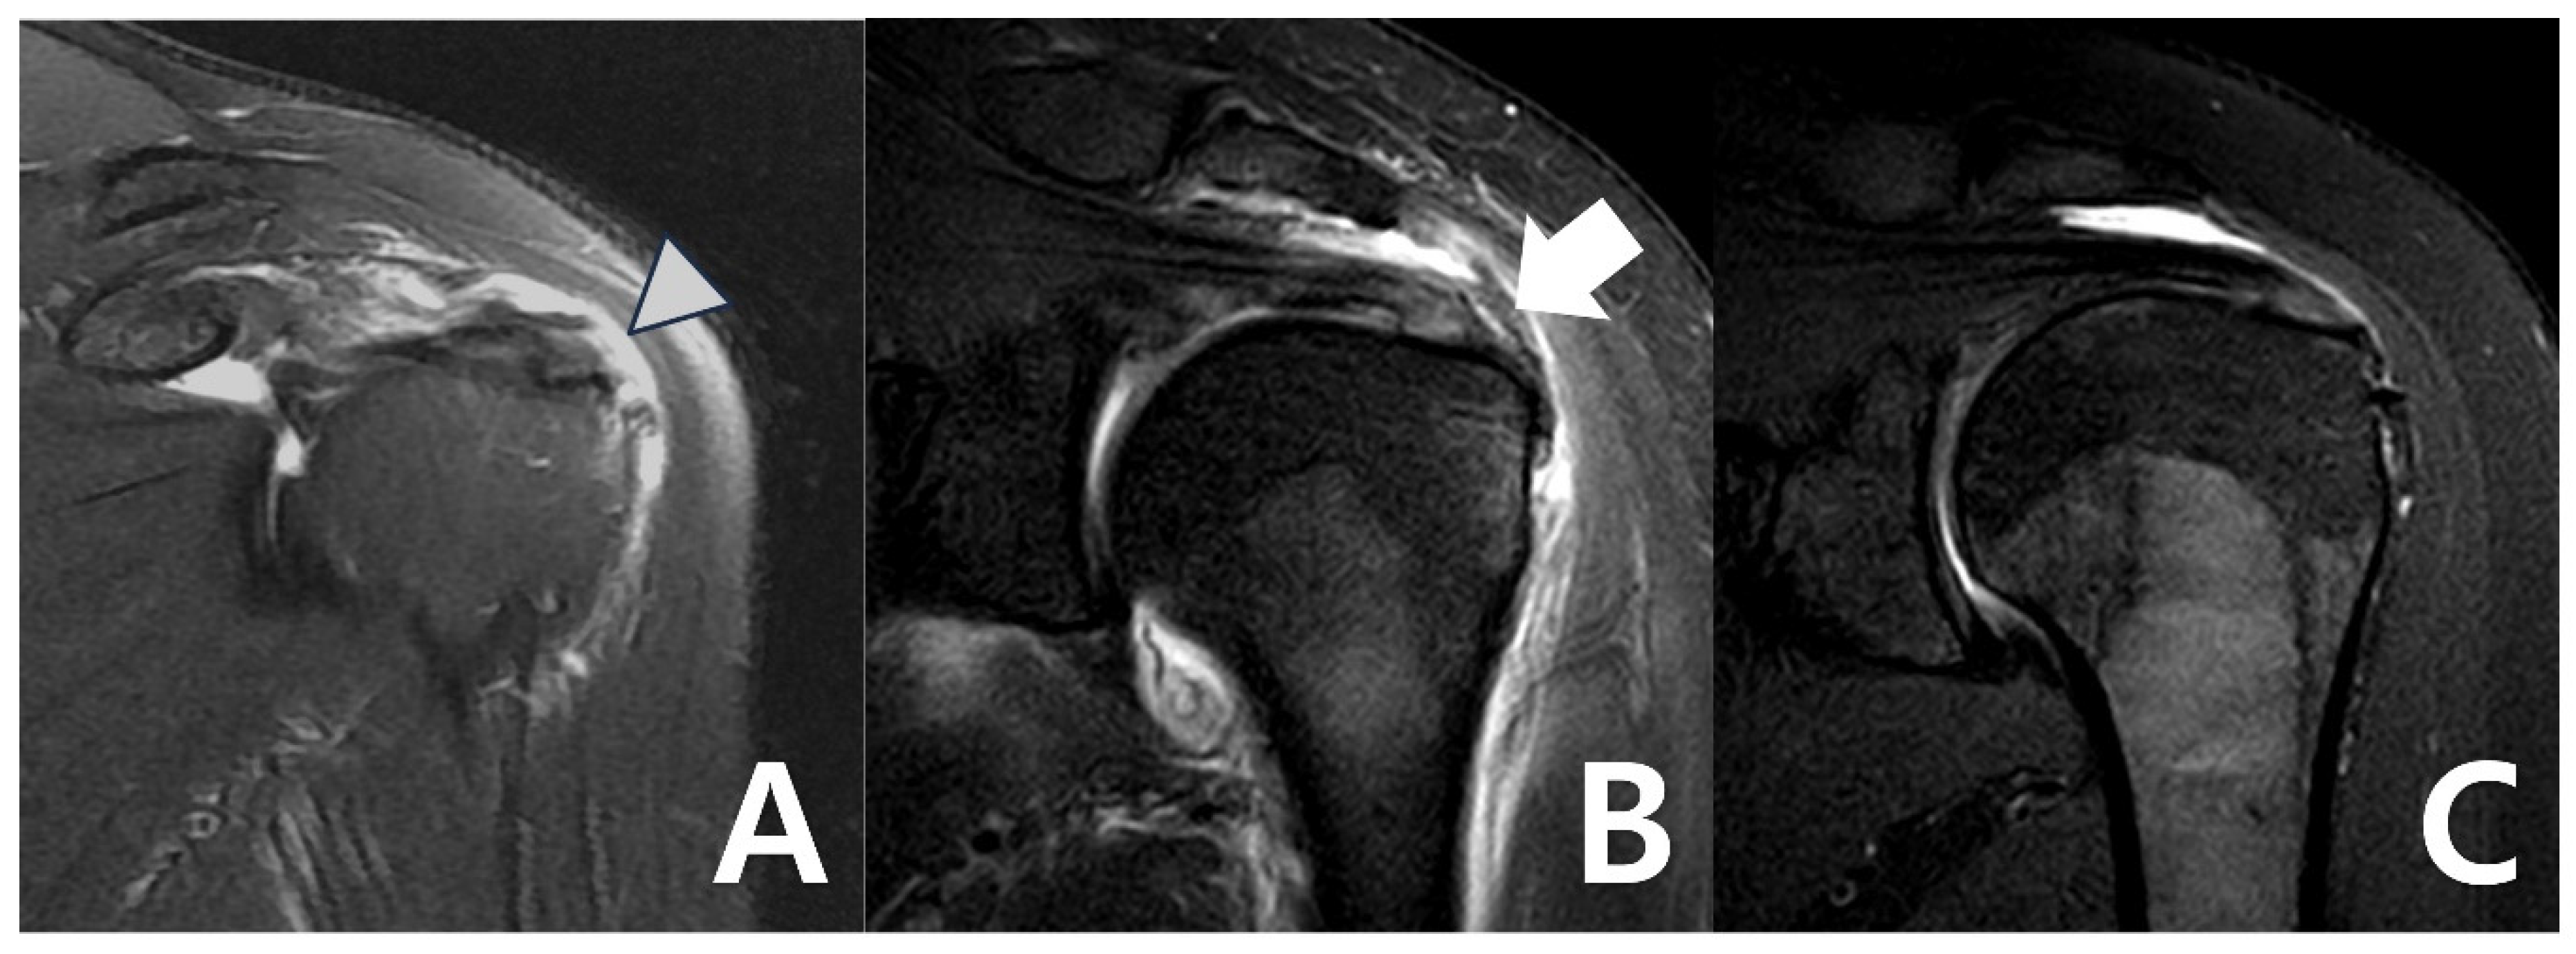

Figure 3. (A) Bursal-side partial-thickness supraspinatus tear with subacromial spur was observed on the preoperative magnetic resonance imaging. (B) Bioinductive collagen implant located on the tendon was observed in a postoperative magnetic resonance image. (C) A magnetic resonance image 6 months after surgery showed that the bio-inductive collagen implant was absorbed, and the bursal-side partial tear was fully recovered.

At 6 months and 12 months after surgery, MRI and ultrasonography were used to examine bioinductive collagen implant integration and assess the condition of the tendon tissue. MRI helped assess tendon integrity and healing, including continuity, signal changes, and possible problems, such as delamination or retear. Ultrasonography was used to offer real-time imaging of the implant’s condition (Figure 3). Radiologic assessments using MRI and ultrasonography revealed no evidence of graft failure or retear at any postoperative stage. Serial images demonstrated continuous tendon remodeling and integration of the bioinductive collagen implant into the native rotator cuff tissue. In this study, radiological evaluation after REGENETEN implantation was conducted using MRI and ultrasound findings. Regeneration was assessed based on the absence of discontinuity, fluid signal intensity, or signs of retear at the graft site on both MRI and ultrasound. Additionally, a progressive change to a homogeneous low signal on T2-weighted MRI images and a continuous, homogeneous echotexture on the ultrasound, along with an observed increase in tendon thickness of approximately 2.0 mm compared to preoperative images, were considered indicative of successful regeneration. Radiological assessments were independently performed by a board-certified radiologist with over 16 years of clinical experience.

The surgeon identified a bursal-side partial-thickness rotator cuff tear and carefully examined the lesion to rule out full-thickness involvement (Figure 2A). To preserve the native rotator cuff, frayed tendon tissue was selectively removed using a shaver and radiofrequency alation device. Afterward, the coracoacromial ligament was released and acromioplasty was performed with a burr and high-speed shaver to address the acromial spur, which contributes to subacromial impingement and tendon degeneration [13].

After establishing a superior anchor portal, a lateral working portal was created for insertion of the bioinductive collagen implant (REGENETEN, Smith & Nephew, London, UK). Using the manufacturer-provided delivery system, the implant was deployed directly onto the degenerative rotator cuff tissue and secured in position. Final arthroscopic assessment confirmed stable positioning and adherence of the implant prior to closure (Figure 2B).